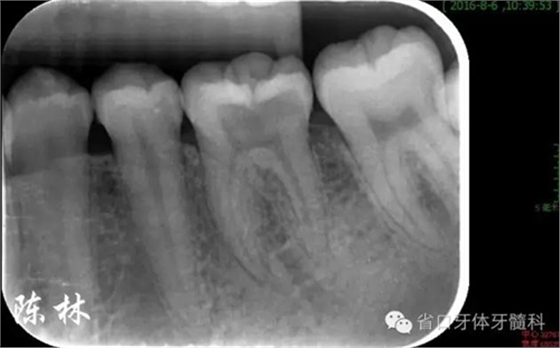

(圖2)術(shù)前根尖片:示36齲損及髓,根周無明顯低密度影